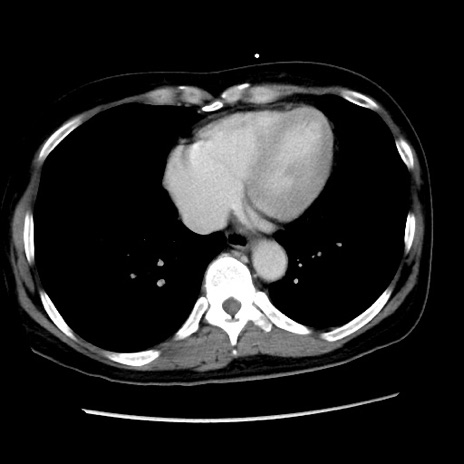

症例10(横断像)

【症例】 50歳代女性

【主訴】 腹痛

【現病歴】前日生レバーを食べた。今朝に排便あり。 昼前に突然発症の腹痛を生じ、当院救急外来を受診した。

【既往歴】 子宮筋腫にてで子宮全摘後

【身体所見】 意識清明、腹部:平坦、軟、下腹部やや左を中心に圧痛・反跳痛あり、筋性防御あり

【データ】WBC 7800、CRP 0.07